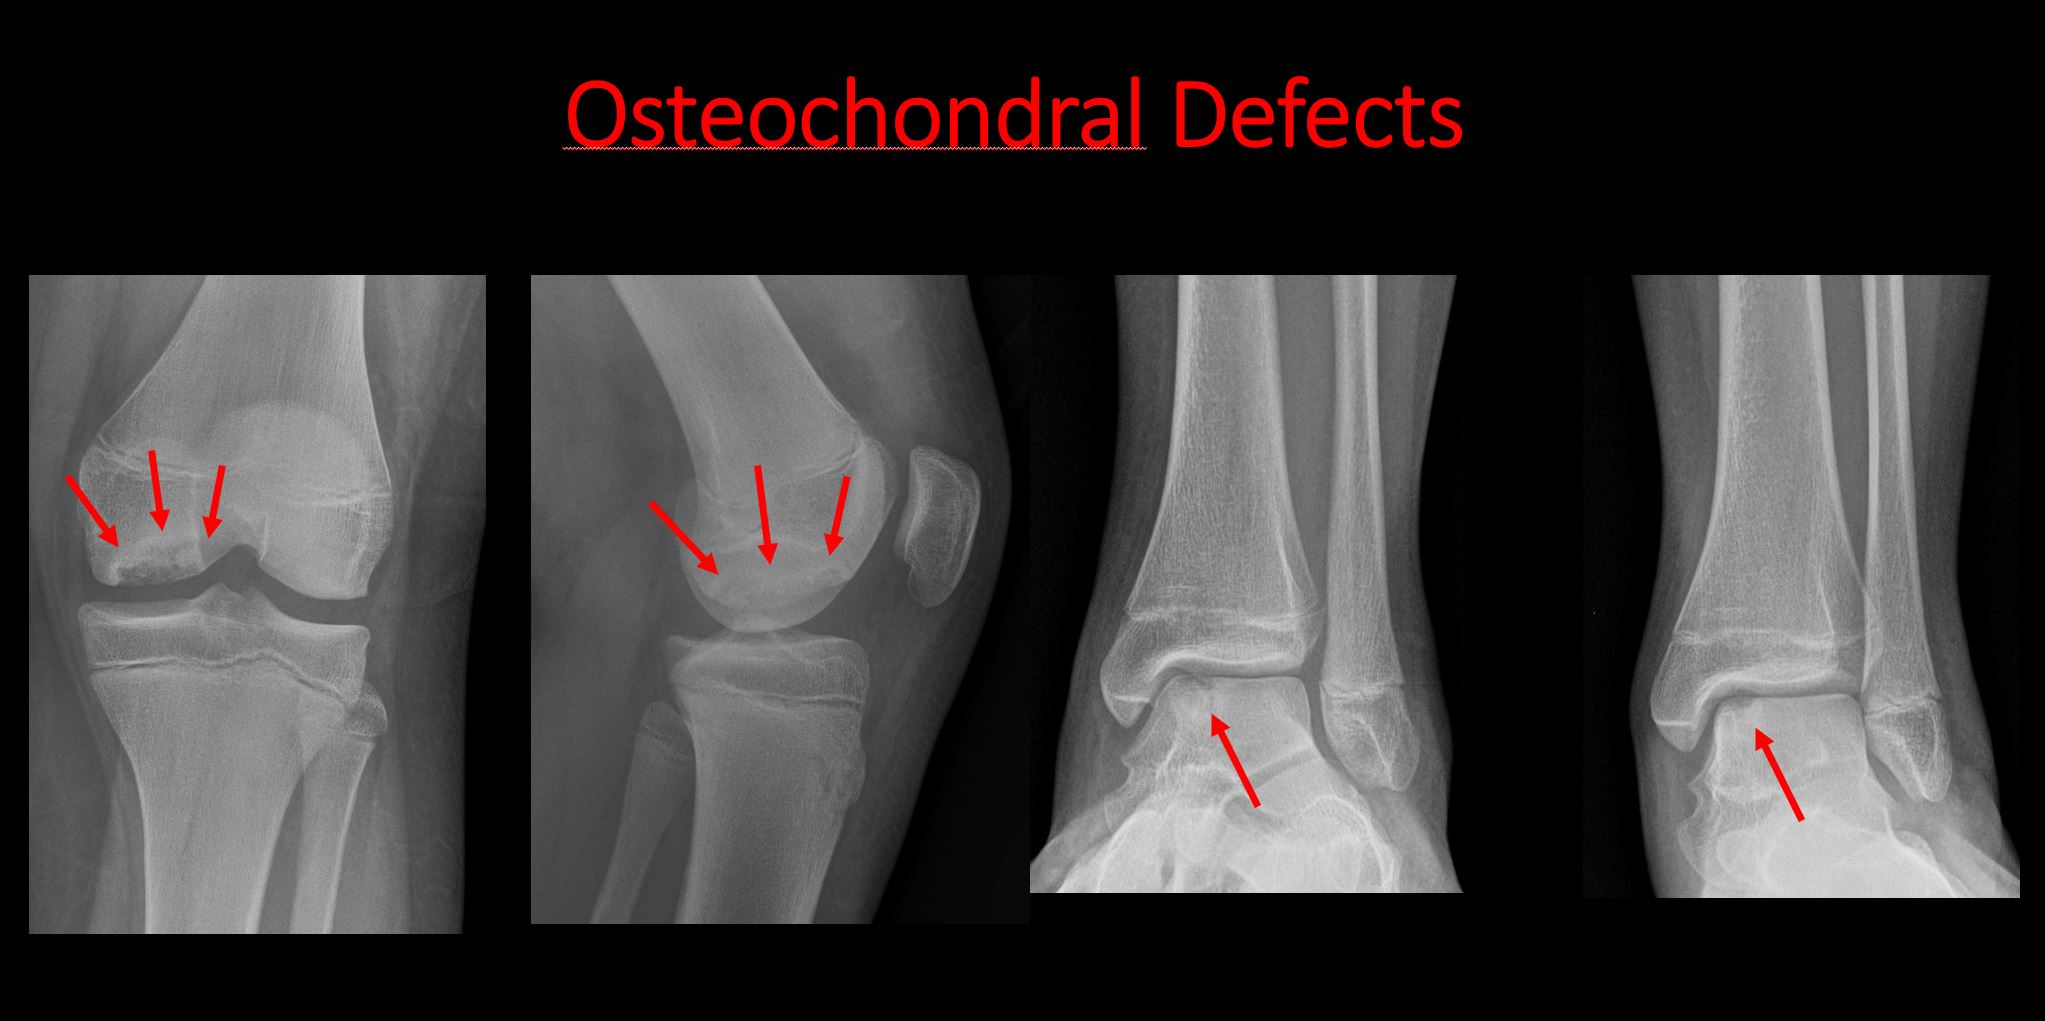

There is linear or irregular lucency, or increased density, cortical depression, flattening, or collapse, with or without cortical disruption or thickening, which may be from a compression or impaction fracture, stress or insufficiency fracture, osteonecrosis (e.g. Legg-Calve-Perthes), other fracture, or from growth recovery lines. |

Yes | NA |

The epiphysis or subchondral bone is fractured, interrupted, flattened, compressed, impacted, displaced, or otherwise abnormal. |